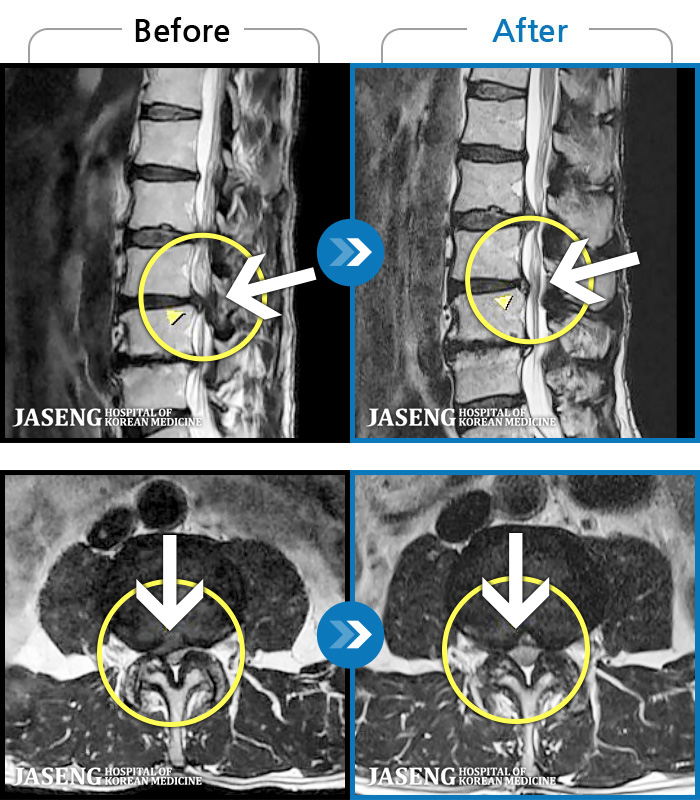

MRI ġ

1,304 MRI ũ ʸ Ȯϼ.